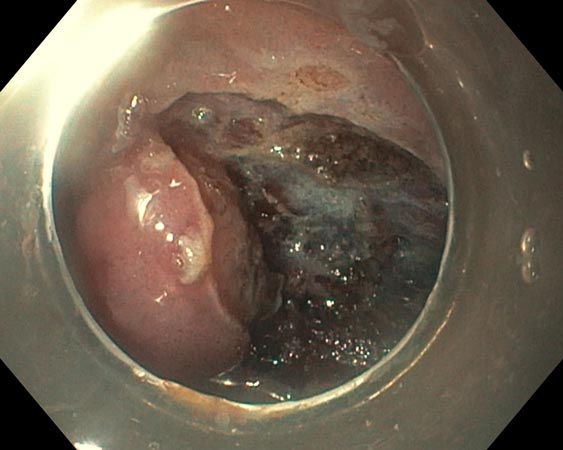

До проведения ESD выполняли эндоскопическую оценку образований в соответствии с Парижской классификацией, классификацией ямочного рисунка (Kudo S., 1996), сосудистого рисунка (Sano Y., 2010). Пациентам с подслизистыми образованиями выполняли эндосонографию прямой кишки и биопсию с иммуногистохимическим исследованием. В ходе эндосонографии выявлены гипоэхогенные образования размерами 0,6 и 0,8 см с интактным мышечным слоем и отсутствием увеличенных регионарных лимфатических узлов (рис. 1, 2).

Рис. 1. Подслизистое новообразование прямой кишки

Рис. 2. Эндосонограмма подслизистого новообразования прямой кишки